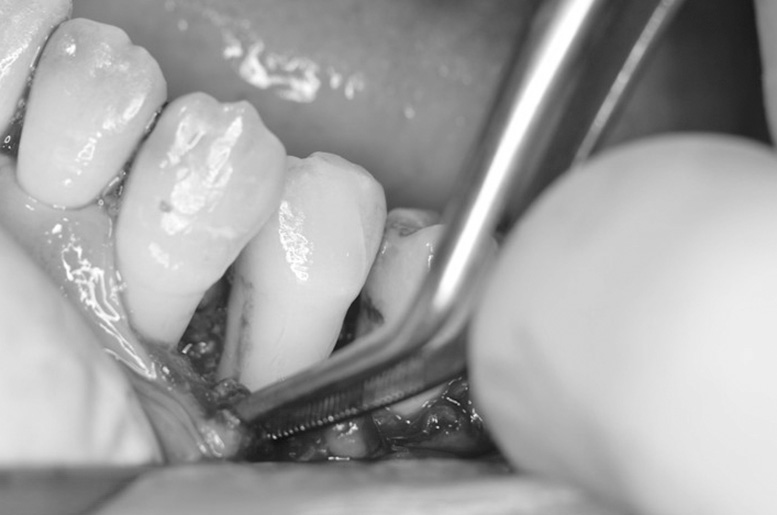

歯周再生療法 精密根管治療 歯周矯正治療 ジルコニアセラミック治療

Before

矯正治療

After

治療期間・回数

約3年・約20回

費用

1,400,000円(歯周矯正治療も含む)

治療のリスク

詰め物・被せ物の調整が難しく、割れた場合は再治療が必要。